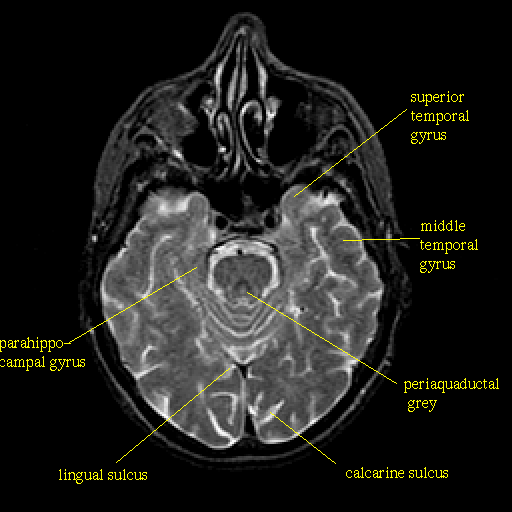

T2-weighted structural MR: Slice 18

Slice 18